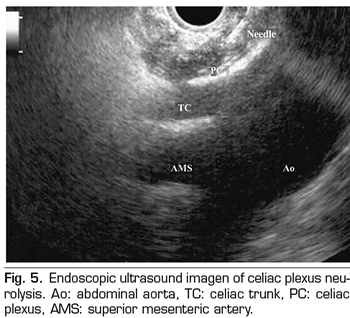

ENDOSCOPIC ULTRASOUND NEUROLYSIS OF THE CELIAC PLEXUS

Endoscopic ultrasound offers the advantage of larger visualization of the celiac plexus at a short proximity, allowing larger precision and safety in the administration of the neurolytic agent and avoiding injection into vascular structures through the use of Doppler (37) (Figure 5). However, the studies supporting endoscopic ultrasound neurolysis, considered similarly to percutaneous technique as a rescue therapy, are limited to retrospective uncontrolled studies (38). Pauli et al. published a meta-analysis that concludes that this technique achieves an 80% pain reduction in patients with pancreatic cancer (39). Some studies show a slight decrease in opioid consumption, but without strong scientific evidence.

Regarding adverse effects, they are reported in a limited series of retrospective publications and case series, being hypotension (11%), diarrhea (18%), and transient abdominal pain (1.5 to 8%) described (37). Theoretically, this technique is safer, with its anterior approach through the gastric wall and direct passage of the needle to the plexus visualizing the vessels, without having to cross the retrocrural space (41). Even so, fatal complications have also been published with this technique. Gimeno-García et al. (42) described the first complication of thrombosis and vasospasm of the celiac artery that produced a multiorganic ischemia and the death of the patient. Since then, this complication has been published in 2 other studies, which also ended in death (43,44). Other adverse effects described are retroperitoneal bleeding and 2 cases of paraplegia.

Among the contraindications related to this technique the following are found: the presence of gastric or esophageal varix - since they increase the risk of bleeding-, an unstructured anatomy, direct tumor invasion of the plexus, and congenital malformations of the celiac trunk or of the superior mesenteric artery.